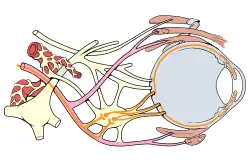

| Eye nerves diagram | |

Oculomotor nerve palsy or oculomotor neuropathy[1] is an eye condition resulting from damage to the third cranial nerve or a branch thereof. As the name suggests, the oculomotor nerve supplies the majority of the muscles controlling eye movements (four of the six extraocular muscles, excluding only the lateral rectus and superior oblique). Damage to this nerve will result in an inability to move the eye normally. The nerve also supplies the upper eyelid muscle (levator palpebrae superioris) and is accompanied by parasympathetic fibers innervating the muscles responsible for pupil constriction (sphincter pupillae). The limitations of eye movement resulting from the condition are generally so severe that patients are often unable to maintain normal eye alignment when gazing straight ahead, leading to strabismus and, as a consequence, double vision (diplopia).